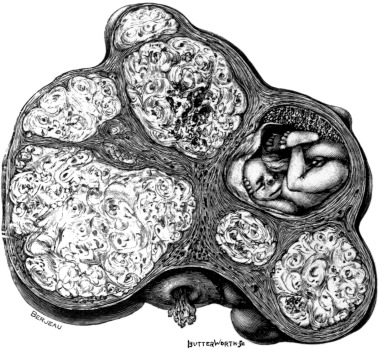

| 22. | A Uterus distorted by Fibroids | 76 |

| 23. | A Gravid Uterus in Sagittal Section | 79 |

| OPERATIONS UPON THE UTERUS DURING PREGNANCY, PARTURIENCY, AND PUERPERY | |

| Cæsarean Section, 69; Immediately after the Death of the Mother, 72. Ovariotomy and Hysterectomy during Pregnancy and in Labour, 73. Ovariotomy during the Puerperium, 76. Fibroids and Pregnancy, 77. Pregnancy with Cancer of the Cervix, 82. Concurrent Uterine and Tubal Pregnancy, 82. Pregnancy with Tumours growing from the Pelvic Walls, 83. Operations for Puerperal Sepsis, 83 | 69–85 |